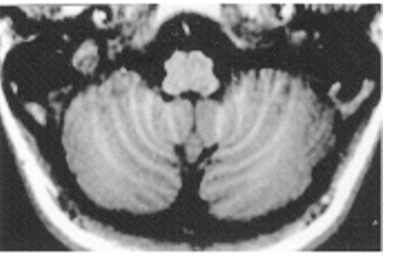

A

midbrain

pons

medulla